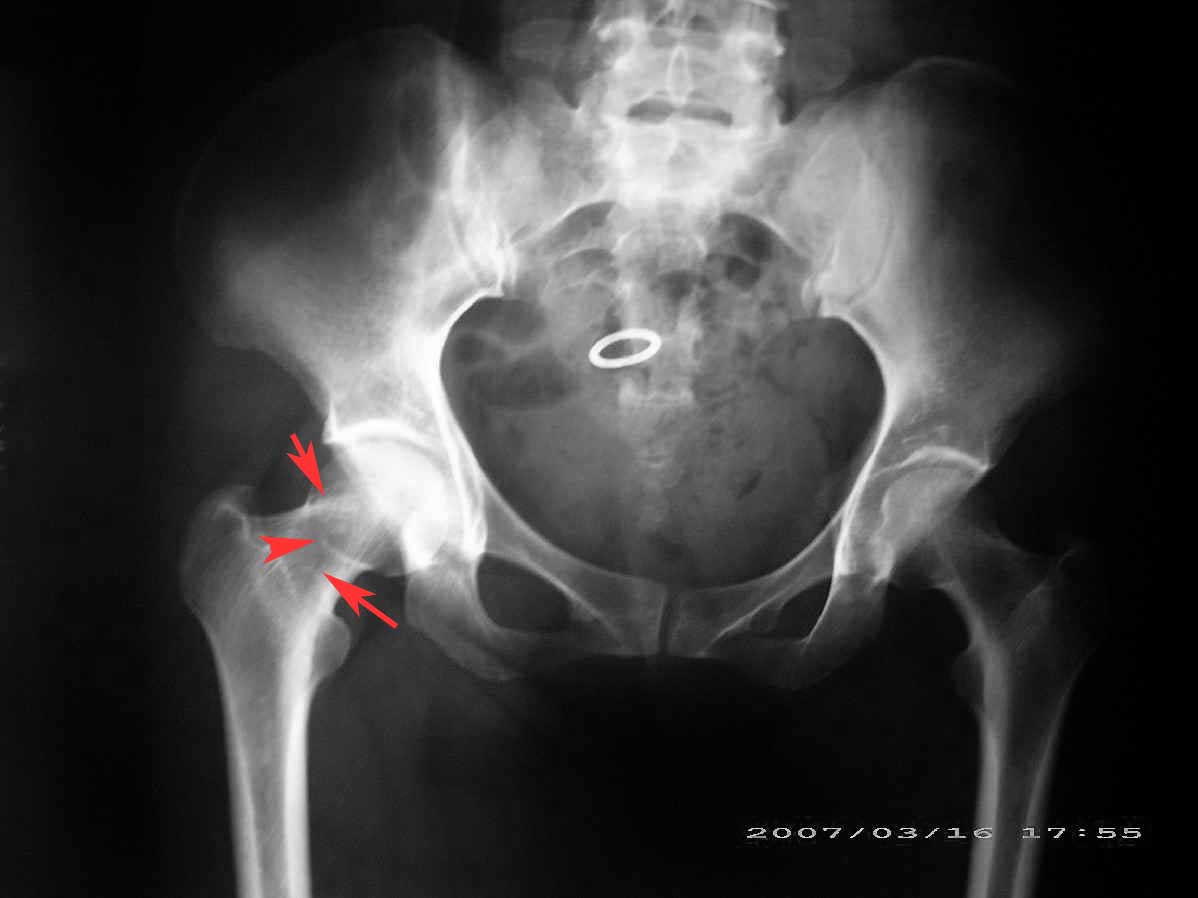

患者,女,因外伤就诊。摄骨盆及右股骨。当时报告骨盆未见明显异常,右股骨中段粉碎性骨折。五天后行股骨中段骨折内固定手术,术中摄床边片示股骨颈骨折。现把术前和术中图像上传。请大家高诊,分析股骨颈骨折是术前漏诊还是其他原因。术前骨盆片右股骨颈显示欠佳是由于股骨中段骨折无法将股骨颈完全显示。

现在我向大家请教,股骨中段粉碎性骨折的同时股骨颈也会骨折吗,另外如图所示该患者股骨颈骨折线是我们常见的由外伤引起的骨折线吗。

回头看术前片,可见一低密透光区.

楼主给我们大家提供了非常好的片子,感谢!该片股骨颈的骨折术前看不到骨折。这个和体位也有关,但是我们都知道,那些标准的体位是给健康人设计的,外伤比较重的往往都无法标准投照。不知道同行们有没有这样一种感受:发现明显的问题了,就心里比较踏实了,舒坦了,就不容易对其它细节仔细观察了。如果没有发现明显的问题,就仔细的翻来覆去的看。所以这个片子给我们很大的教训:仔细阅片!即便是已经发现问题了。如果非要给鸡蛋里面挑骨头,我认为楼主忽略了右髋关节囊的肿胀,诊断报告应该提一下。外伤的病人我最怕股骨颈的漏诊,一般我都要看软组织。我是一个小医院的,我深有感触,发现骨折不是功劳,而漏诊却是事故,还遭受别人耻笑:放射科的连骨头断没断都看不出来!

关于楼主说的骨折线的形态,的确和一般外伤的有种不太一样的感觉,上方裂隙较明显,下方骨皮质“连续”,我认为成年人应该是全部断了的,不全骨折的可能性非常非常小,该片恰好无法全部显示骨折线。骨折线的形态不能判定术前还是术后骨折。以上只是个人小小看法,请各位老师指正为谢!